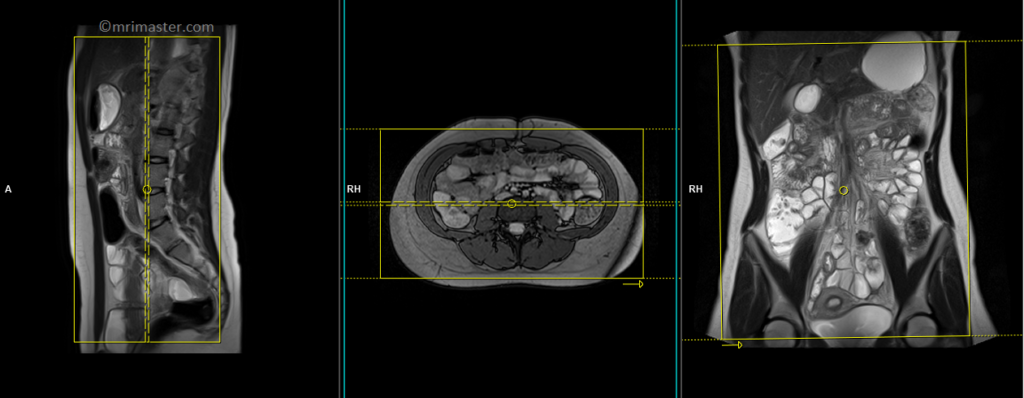

T1 VIBE DIXON \ T1 flash fat sat 3d 1-1.5 mm axial post contrast

Plan the axial slices on the coronal image, position the block horizontally across the abdomen as shown, and ensure that the positioning block is also checked in the other two planes. Establish an appropriate angle horizontally across the abdomen in the sagittal plane. The slices must be sufficient to cover the entire abdomen and pelvis from the stomach to the pubic symphysis. To prevent wrap-around artifacts, phase oversampling, and in the case of 3D blocks, slice oversampling must be used. Instruct the patient to hold their breath during image acquisition. (In our department, we instruct the patients to breathe in and out twice before giving the “breathe in and hold” instruction.)

The axial scan is performed as two separate blocks with a 10-25% slice overlap between them. The scan is performed this way to avoid any RF inhomogeneity-related artifacts by conducting the scans at the isocenter of the magnet. Use the composing function in the scanner to stitch the two blocks together.

Protocol Parameters T1 FLASH Axial

TR 3-4 | TE 1-2 | FLIP 12 | NEX 1 | SLICE 2 MM | MATRIX 320X320 | FOV 350-420 | PHASE A>P | OVERSAMPLE 30% | IPAT ON |